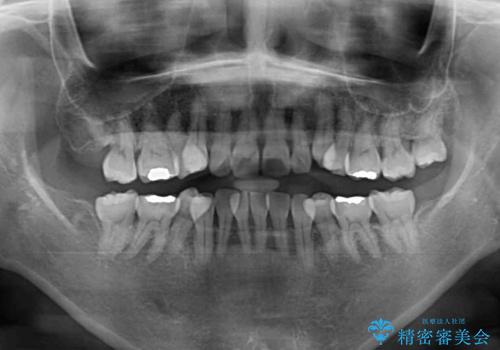

- 小さいころからの歯の変色と矯正治療の後戻りを気にして来院された患者様です。

気になる変色歯を仮歯に変え、その後歯列不正を矯正治療で改善し、最後にオールセラミッククラウンにて補綴治療することとしました。

- 治療費の目安: 250万円費用は治療当時の料金となります